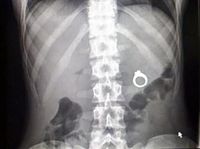

ок проглотил кольцо

Ребенок проглотил кольцо 116 фото